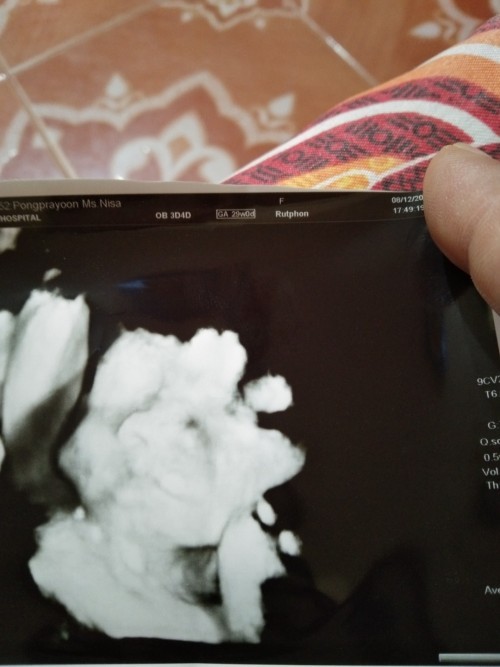

บ้านนี้10กพ.ได้ ลูกสาวท้องแรกค่ะ